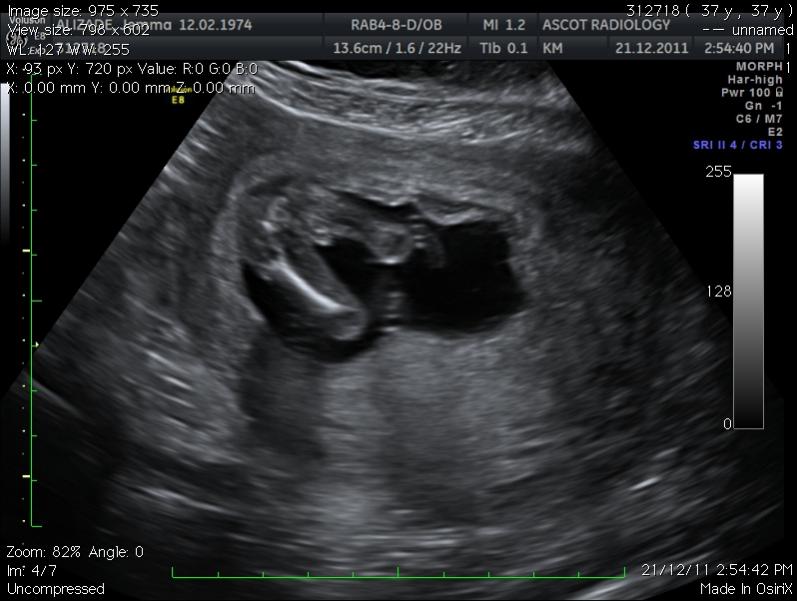

oooppps just posted this in confirmed girl pics forum - new here! Can any of you guys give me advise on my potty shot taken at 15 wks and 6 days. They thought it was a boy and after 3 boys i was praying for a girl this time! I am so devastated if it's a boy...

Attachment 993